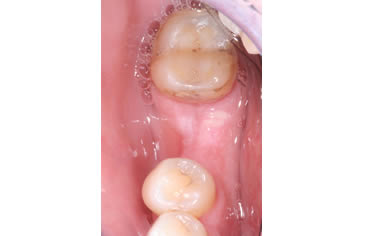

More back teeth replaced by dental implants

Case Four (4 images)